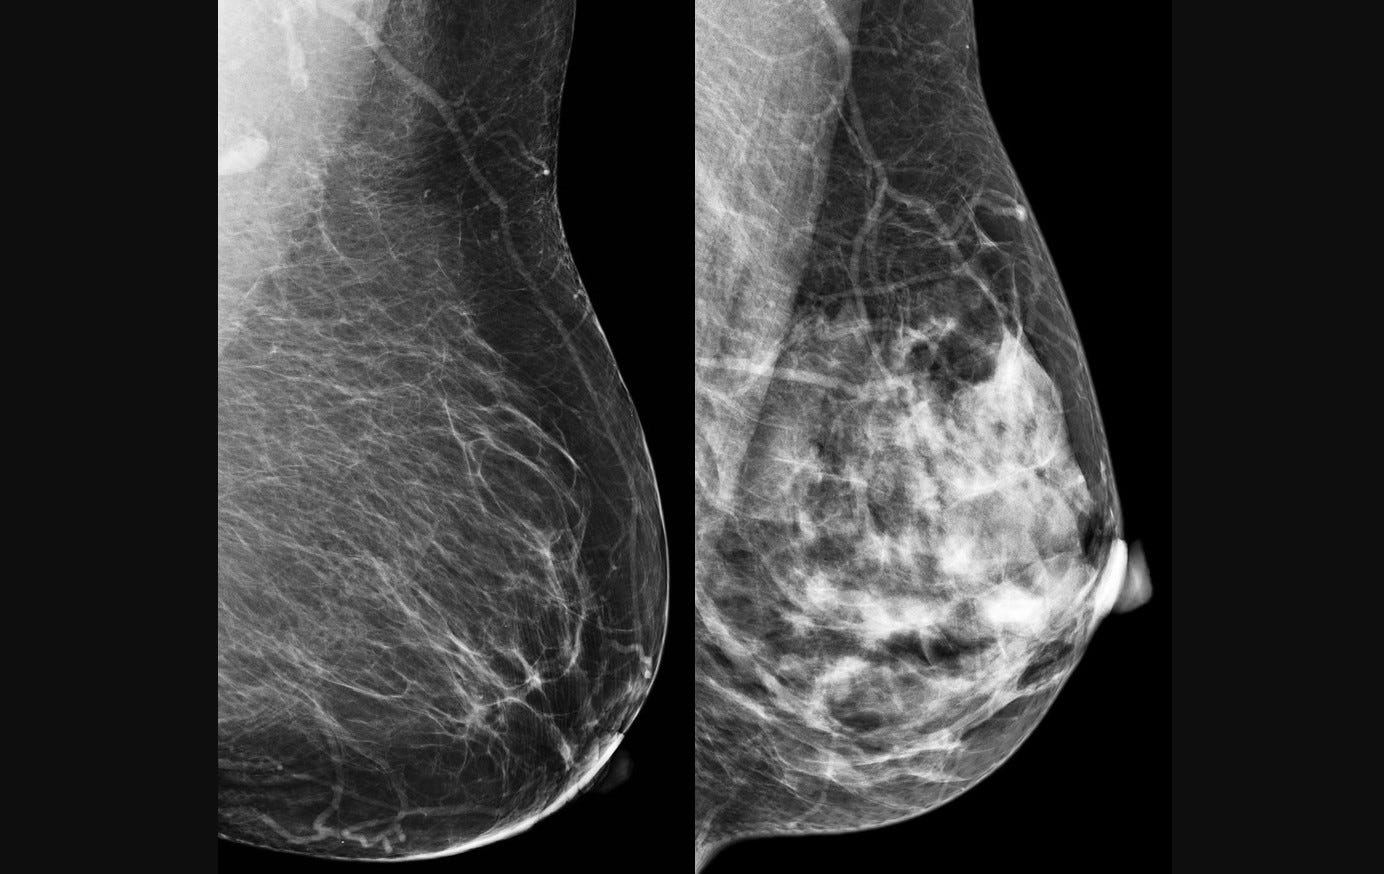

Câncer de mama é a principal causa de morte por tumor na população feminina (imagem: CDC/reprodução)